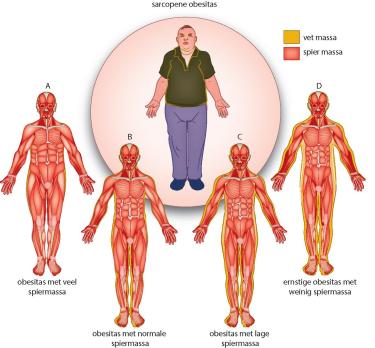

Het komt steeds vaker voor dat mensen sarcopene obesitas hebben, dat is de combinatie van obesitas en spierzwakte. Dit gaat gepaard met risico’s op fysieke beperkingen en postoperatieve complicaties. Deze patiënten hebben geen baat bij een simpel advies om af te vallen, aangezien ze dan in een vicieuze cirkel van verdere achteruitgang kunnen komen als gevolg van verdere afbraak van spieren. Door middel van enkele fysieke testen is sarcopene obesitas te herkennen. Met een gecombineerde interventie van kracht- en conditietraining en eiwitrijke voeding zijn de spiermassa en ‑functie en het fysiek functioneren van deze patiënten te verbeteren